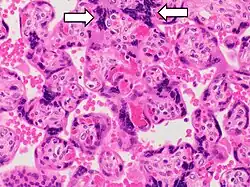

- Increased syncytial knots

- Villi capillaries occupying about 50% of the villi volume or when <40% of capillaries are on the villous periphery